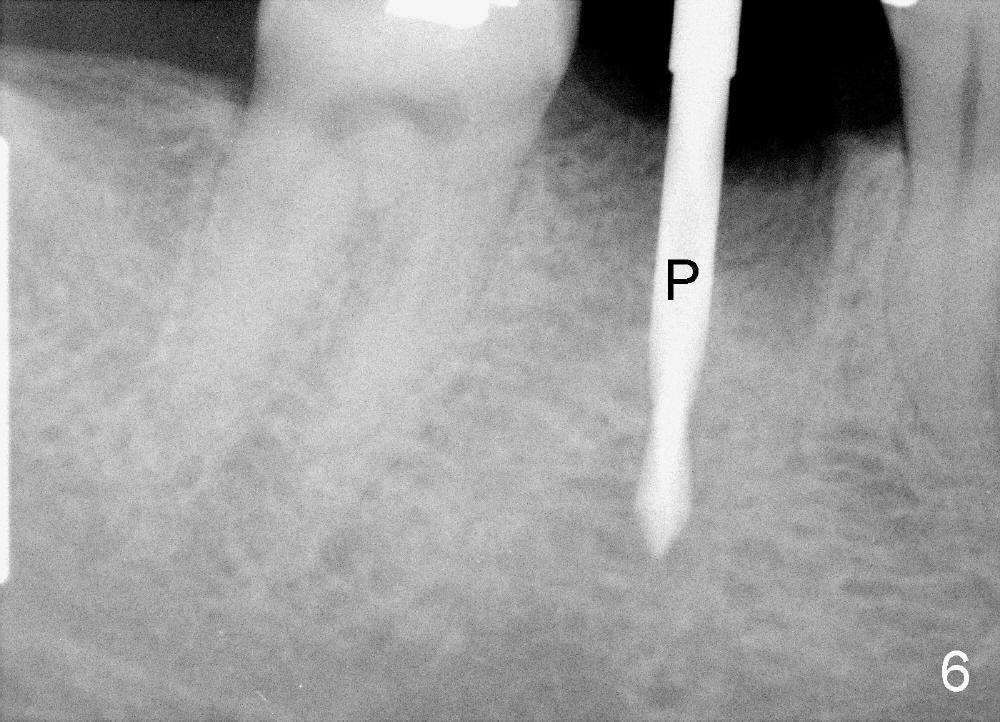

A 38-year-old lady agrees to have implant placement 7 years after loss of the crown of the lower right first molar (Fig.1,2). When the tooth is extracted, the septum is found to be low (Fig.3,4). To confirm it, a PA is taken (Fig.5). To initiate an osteotomy in the septum, it is trans-sectioned with thin osteotomes as shown in Fig.4 insert (black line). A 2 mm pilot drill is placed in the septum (Fig.6: P). The osteotomy is enlarged by 2.5-4.0 mm reamers (Fig.7,8), followed by insertion of 6x17 mm tapered tap at the depth 14 mm (Fig.9). The osteotomy is further enlarged by 4.5 and 5.0 mm reamers. A 6.0x14 mm one piece implant is placed initially. The trajectory is not ideal. A 6.0x14 mm one piece implant is placed initially. The trajectory is not ideal. The implant is removed from the osteotomy partially and reinserted with improved trajectory (Fig.11, compare to Fig.10 (red line)). Primary stability is high. There is not much bone mesiodistally so that the trajectory is easily changed in that direction. After abutment preparation, mixture of autogenous bone (harvested from reamers) and allograft is placed in the residual mesial and distal sockets (Fig.12). To contain the bone graft, an immediate provisional is placed (Fig.13 P). The occlusal plane of the provisional is significantly lower than that of the adjacent teeth to avoid micromovement of the implant. The patient is advised to eat soft food on the left side. Six days postop, the patient returns for prophy. The provisional is removed; the bone graft appears to be incorporating into the socket (Fig.14). After recementation, the provisional remains in place for 3.5 months; PA shows increased bone density in the mesial and distal sockets (Fig.15, compare to Fig.5,11). Due to insurance coverage, the patient defers fabrication of definitive restoration for at least 7 months. The immediate provisional is finally lost 8.5 months postop: the gingiva attaches to the 1-piece implant (Fig.16), while the density of the mesial socket increases (Fig.17 *) with formation of the cortex (lamina dura) coronally (v). Before the provisional (Fig.18 P) is removed for cementation of the definitive restoration, black shadow (*) is noted over the buccal gingiva. It is partially due to buccal placement (Fig.19) and partially due to buccal atrophy over a period of 10.5 months postop. How to prevent buccal placement? Positioning the first pilot drill in the septum buccolingually is a key. Eleven months post crown (Fig.20 C) cementation, the black shadow remains, but there is no tenderness. If the implant threads are immediately underneath the periosteum, there is tenderness.